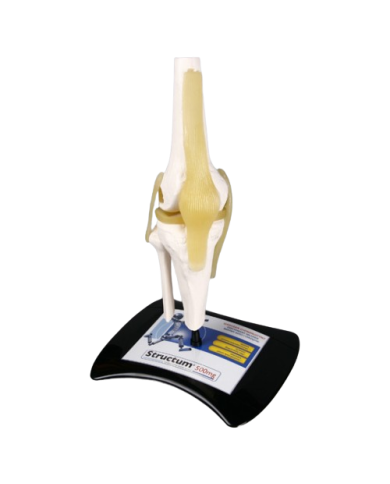

Modello anatomico PER FORNITURE CASE FARMACEUTICHE

Modello anatomico PER FORNITURE CASE FARMACEUTICHE

Modello anatomico PER FORNITURE CASE FARMACEUTICHE

Modello anatomico PER FORNITURE CASE FARMACEUTICHE

Modello anatomico PER FORNITURE CASE FARMACEUTICHE

Modello anatomico PER FORNITURE CASE FARMACEUTICHE

Modello anatomico PER FORNITURE CASE FARMACEUTICHE

Modello anatomico PER FORNITURE CASE FARMACEUTICHE

Modello anatomico PER FORNITURE CASE FARMACEUTICHE

Modello anatomico PER FORNITURE CASE FARMACEUTICHE

Modello anatomico PER FORNITURE CASE FARMACEUTICHE

Modello anatomico PER FORNITURE CASE FARMACEUTICHE

Modello anatomico PER FORNITURE CASE FARMACEUTICHE

Modello anatomico PER FORNITURE CASE FARMACEUTICHE

Modello anatomico PER FORNITURE CASE FARMACEUTICHE

Modello anatomico PER FORNITURE CASE FARMACEUTICHE

Modello anatomico PER FORNITURE CASE FARMACEUTICHE

Modello anatomico PER FORNITURE CASE FARMACEUTICHE

Modello anatomico PER FORNITURE CASE FARMACEUTICHE

Modello anatomico PER FORNITURE CASE FARMACEUTICHE

Modello anatomico PER FORNITURE CASE FARMACEUTICHE

Modello anatomico PER FORNITURE CASE FARMACEUTICHE